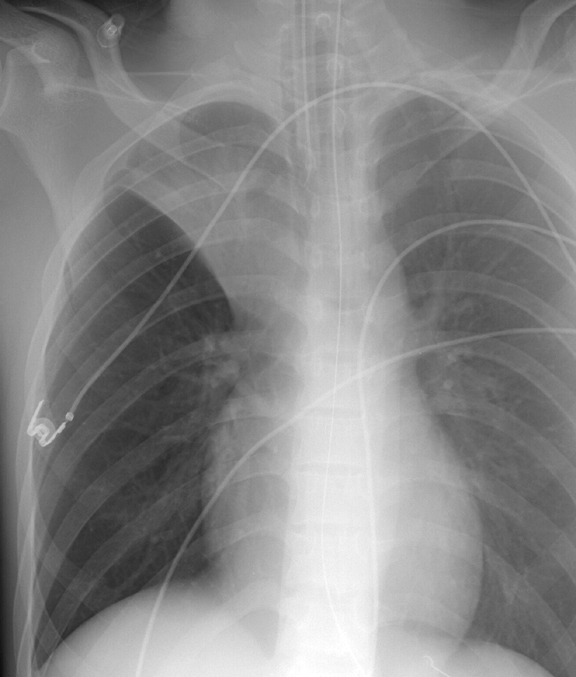

Lobar Collapse

RUL Collapse

RUL Collapse Case 6 PA only

Date: 02/28/2004